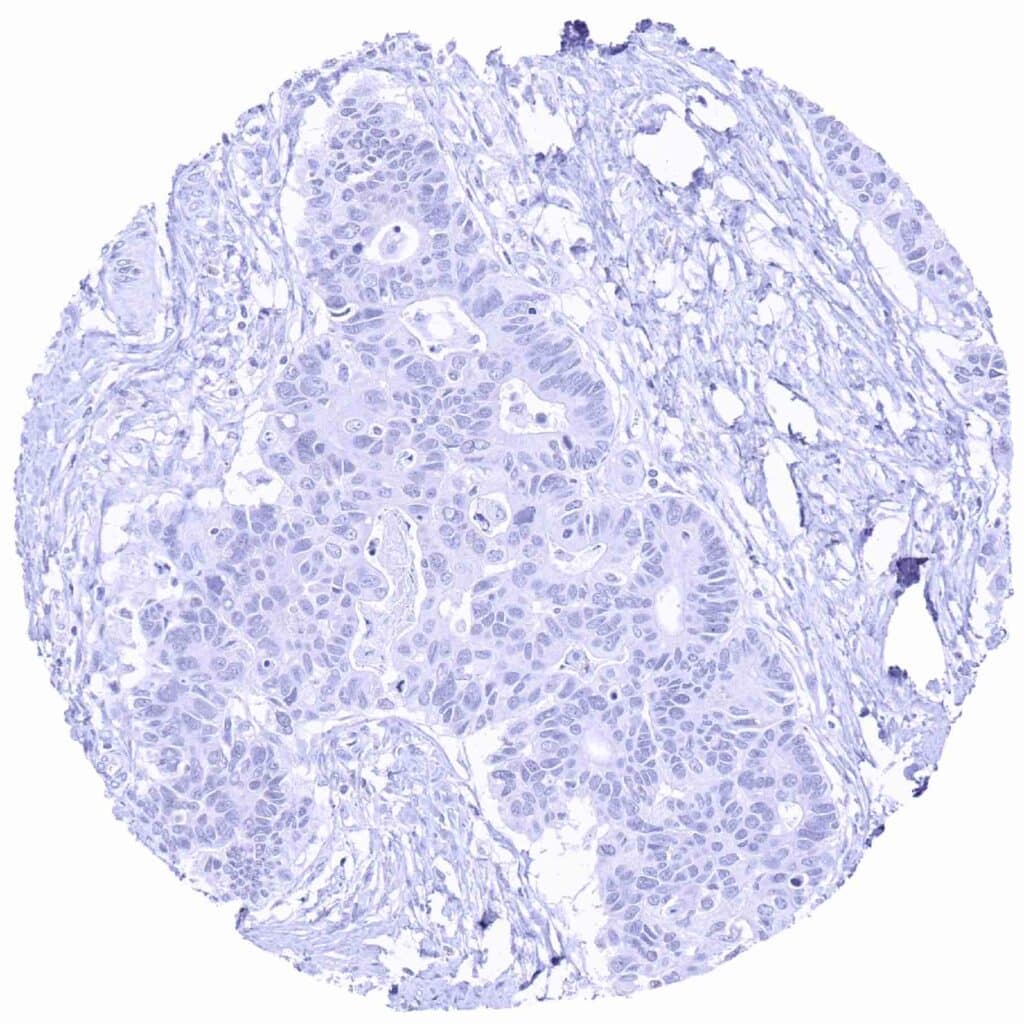

Pancreas – Prostein negative ductal adenocarcinoma

Pancreas – Prostein negative neuroendocrine tumor

Prostate – Prostein negative small cell carcinoma